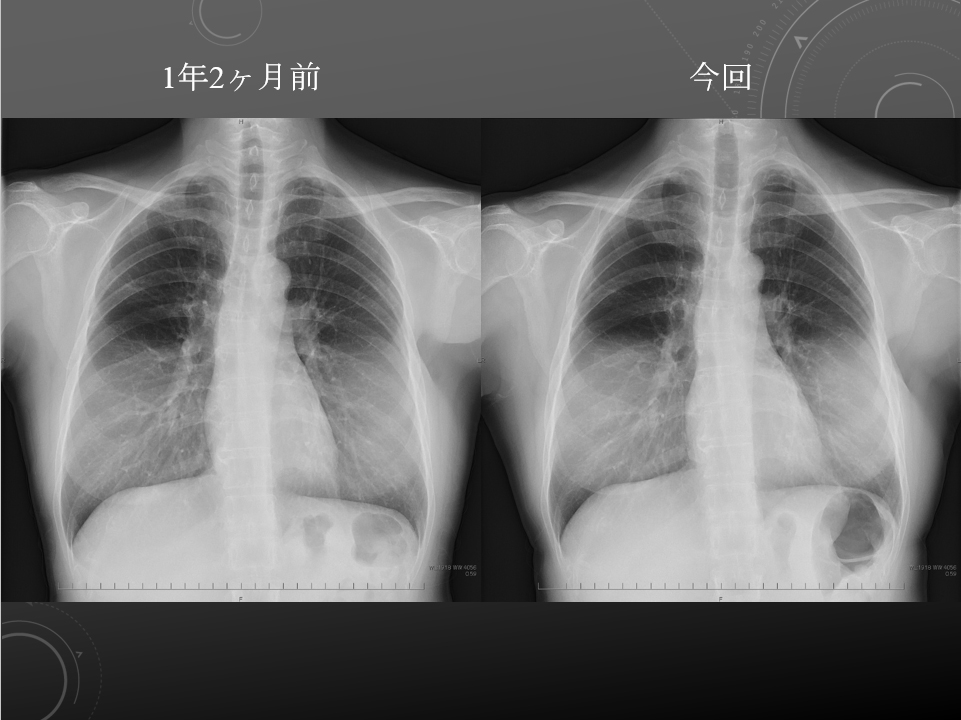

4F 乳癌で化学療法中 MDS 発熱

前回2017年11月20日の胸部単純写真と比較しました。

肺野に明らかな腫瘤影や浸潤影は指摘できません。

両側胸水貯留は指摘できません。

心陰影の拡大は認められません。

肺野に明らかな異常所見は指摘できません。

MDS、乳癌術後

軽度呼吸苦

2017年8月14日と比較しました。

肺野に明らかな活動性病変は指摘できません。

心拡大や胸水貯留は見られません。

骨性胸郭に明らかな異常所見はみられません。